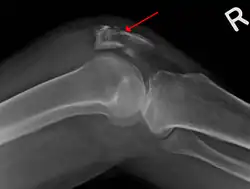

| A fracture of the patella seen on a lateral view | |

It typically results from a hard blow to the front of the knee or falling on the knee.[1]The patella can also be fractured indirectly. For example, a sudden contraction of the quadriceps muscle in the knee can pull apart the patella.[1]Diagnosis is based on symptoms and confirmed with X-rays.[3] In children an MRI may be required.[3]